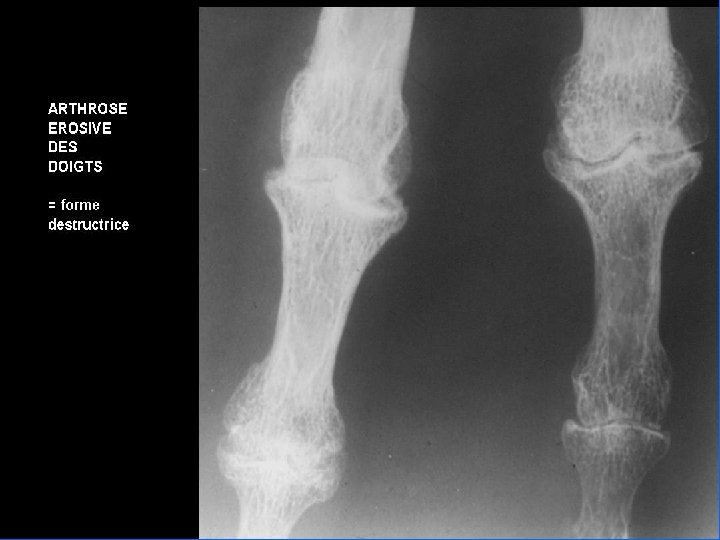

Comment faire le diagnostic ? • Le diagnostic est clinique : déformations typiques • Les radiographies : mains de face – pincement de l’interligne – une ostéophytose latérale en berge, très exubérante responsable des nodosités – géodes sous-chondrales